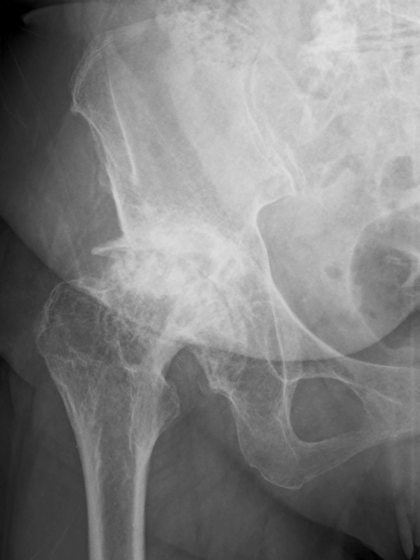

画像検査

X線(レントゲン)検査が基本となり、関節軟骨の厚みの減少(関節の隙間の狭小化)、骨棘(こつきょく:骨のトゲ)、骨嚢胞(こつのうほう:骨の中にできる空洞)の形成などを確認します 。必要に応じて、MRI検査で軟骨や周囲の軟部組織の状態をより詳細に評価します 。血液検査は、他の炎症性疾患との鑑別のために行われることがあります。

病期分類

X線所見に基づき、病気の進行度を前期、初期、進行期、末期のように分類し、それぞれの段階に応じた治療方針を決定します。